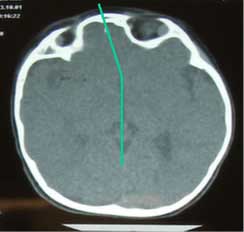

La imagen muestra una craneosinostosis en un niño de 18 meses de edad. Observando el TAC tridimensional es evidente que no es simétrico: el eje craneal se encuentra desviado, la zona de crecimiento se ha sellado, y se ha producido un abombamiento del cráneo hacia atrás y de la cara hacia la izquierda.

- Asimetría craneal evidente en TAC 3D

- Zona de crecimiento sellada prematuramente

- Abombamiento posterior del cráneo

- Desviación de la cara hacia la izquierda